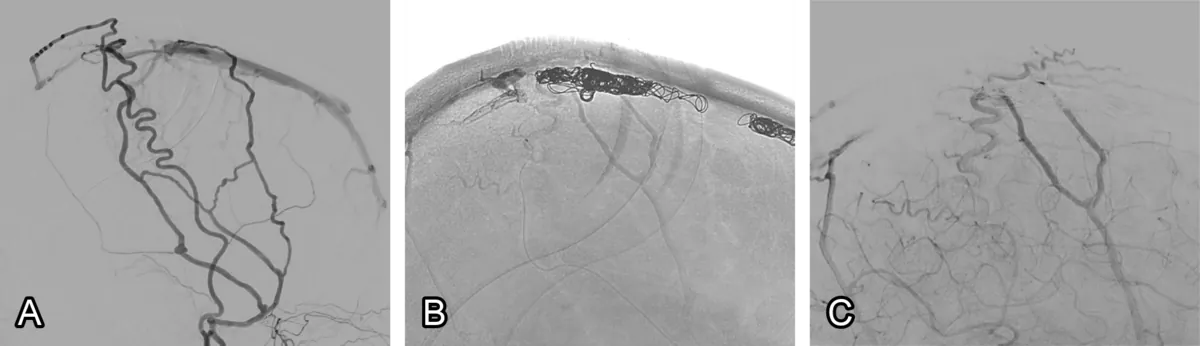

The procedure begins with the insertion of a thin, flexible plastic tube (catheter) into either the femoral artery in the groin or an artery in the wrist. The catheter is advanced through the aorta into the cerebral arteries of the neck and brain. Once the most accessible feeding vessel is identified, additional catheters, including a microcatheter, are introduced to reach the point of the fistulous connection (fig. 1). Embolic material, often glue-like in consistency, is then injected to occlude the DAVF. In some cases, small platinum coils are deployed in addition. The embolic material forms an artificial clot, preventing further abnormal blood flow into the fistula. X-rays are obtained throughout to confirm successful obliteration.

Figure 1: Dural fistula embolisation. (A) A DAVF is seen towards the top of the head. (B) Coils are placed, blocking the blood flow. (C) The fistula is gone at the end of the procedure.